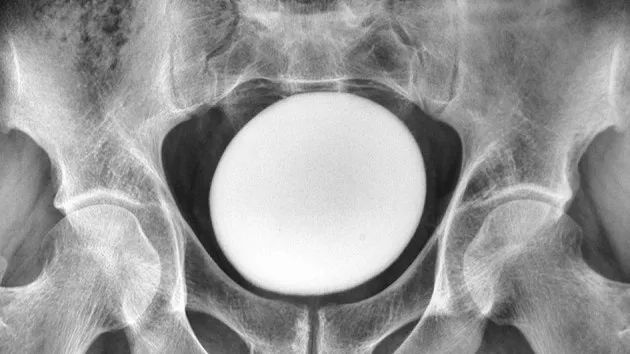

이란에 거주하는 30대 남성의 방광에서 마치 타조알처럼 보이는 커다란 결석이 발견됐다. /사진=-네프로-유롤로지 먼슬리 CC BY 4.0, 라이브사이언스 |

의사들은 환자의 복부를 진찰하던 중 치골 위에서 크고 매끄러우며 단단한 덩어리가 만져져 초음파 검사를 실시했다. 그 결과 환자의 방광 안에 지름 11㎝의 커다란 결석이 있음을 확인했다.

해당 남성은 방광 절개술을 받고 결석을 제거했다. 제거된 결석은 길이 13㎝, 너비 10㎝, 높이 8㎝로 무게만 약 826g에 달한 것으로 알려졌다.